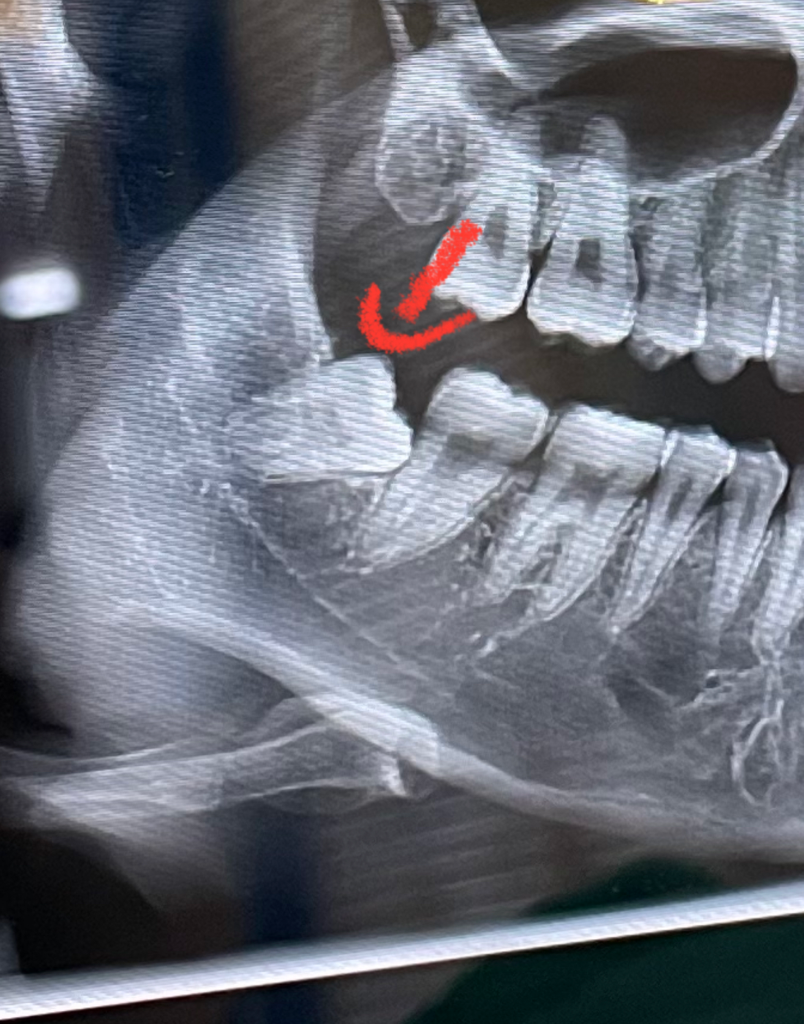

매복 사랑니는 언제 빼는게 좋을까요?

사랑니 4개중 3개 발치 후 1개 남았습니다.

• 1번 째 사진

젊은 나이에 빼는 것을 권해드립니다. 1살이라도 젊은 나이에 발치를 해야 발치 난이도가 높지 않고 추후 문제를 일으킬 가능성이 크지 않습니다. 지금과 같이 앞쪽 어금니를 손상시킬 수 있다면 바로 발치하는 것이 좋습니다.

가능한 빨리 빼기를 권합니다. 지금 사랑니가 사랑니 바로옆 어금니 뒷쪽을 밀고 있기 때문에 손상을 입을 가능성이 많아 보입니다.